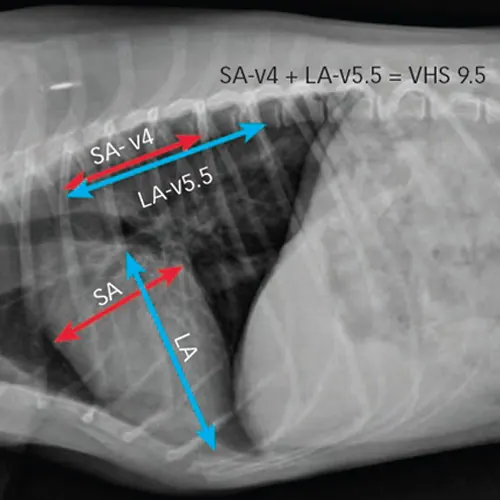

Steps to Measure VHS

1. Measure the long axis (LA) of the heart from top of the left atrium to the tip of the apex of the ventricle (blue arrow).

2. Measure the short axis (SA) of the heart at the widest part of the left and right heart chambers at the level of the coronary groove (red arrow).

3. Transpose the LA and SA dimensions onto the vertebral column and record the corresponding number of vertebrae (V), starting at the cranial edge of T4 moving caudally.

4. Take the sum of the SA and LA vertebral measurements to find the VHS.5. In this patient, the VHS = 9.5.